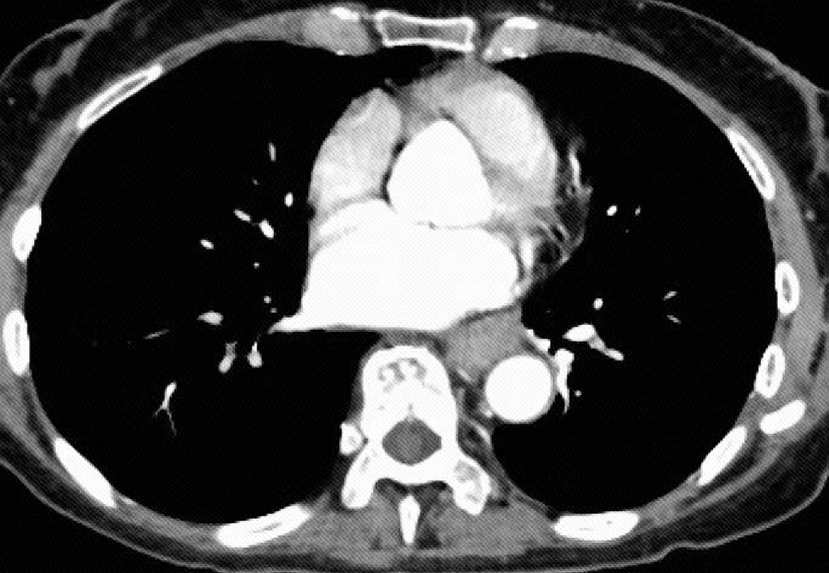

治疗团队首先为谭阿姨实施了“免疫联合化疗”的新辅助治疗方案,旨在缩小肿瘤、降低分期。两个周期后,复查显示肿瘤明显缩小,达到部分缓解,为后续手术创造了宝贵机会。在准确把握手术时机后,团队决定采用达芬奇机器人辅助系统,为患者施行颈、胸、腹三切口食管癌根治术。吴昊介绍,相较于传统胸腔镜手术,机器人系统具备三维高清放大视野、540度仿生旋转器械臂以及自动滤除手部震颤等功能,能在狭小的纵隔空间内实现更精准、稳定的操作,既保障了肿瘤的彻底切除与淋巴结清扫,又最大程度保护了血管、神经等重要组织,显著提升了手术的安全性与彻底性。